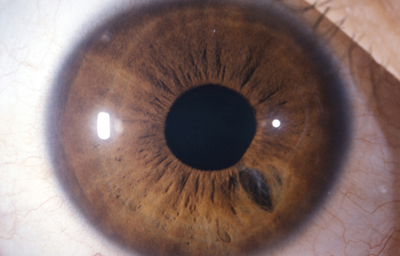

Colobomas

Desde el comienzo del estudio de la embriología del ojo, se ha hecho relación entre el cierre de la Fisura de la Copa Óptica y los Colobomas Oculares.

Se los clasifica como “Típicos” aquellos colobomas infero-nasales, y en general afectan Iris, Cuerpo Ciliar y Coroides. “Atípicos”aquellos situados en cualquier otro lugar del Iris.

Colobomas típicos con diferentes grados de defecto en el desarrollo

Colobomas Atípicos.

Archivo Fotográfico Dr. Francisco Barraquer

Archivo Fotográfico Dr. Francisco Barraquer

Las posibles explicaciones de su origen siguen en discusión y la pregunta es: ¿la causa primaria de los colobomas es Ectodémica o Mesodérmica? Podría tratarse de una falla localizada en una porción del margen ectodérmico de la copa óptica o bien, a una persistencia indebida del mesodermo fetal, que secundariamente inhibiría el crecimiento del ectodermo en contacto con él.

Existen múltiples argumentos relacionados, pero ninguno definitivo. actualmente se habla más de los errores genéticos que pueden producir estos defectos.